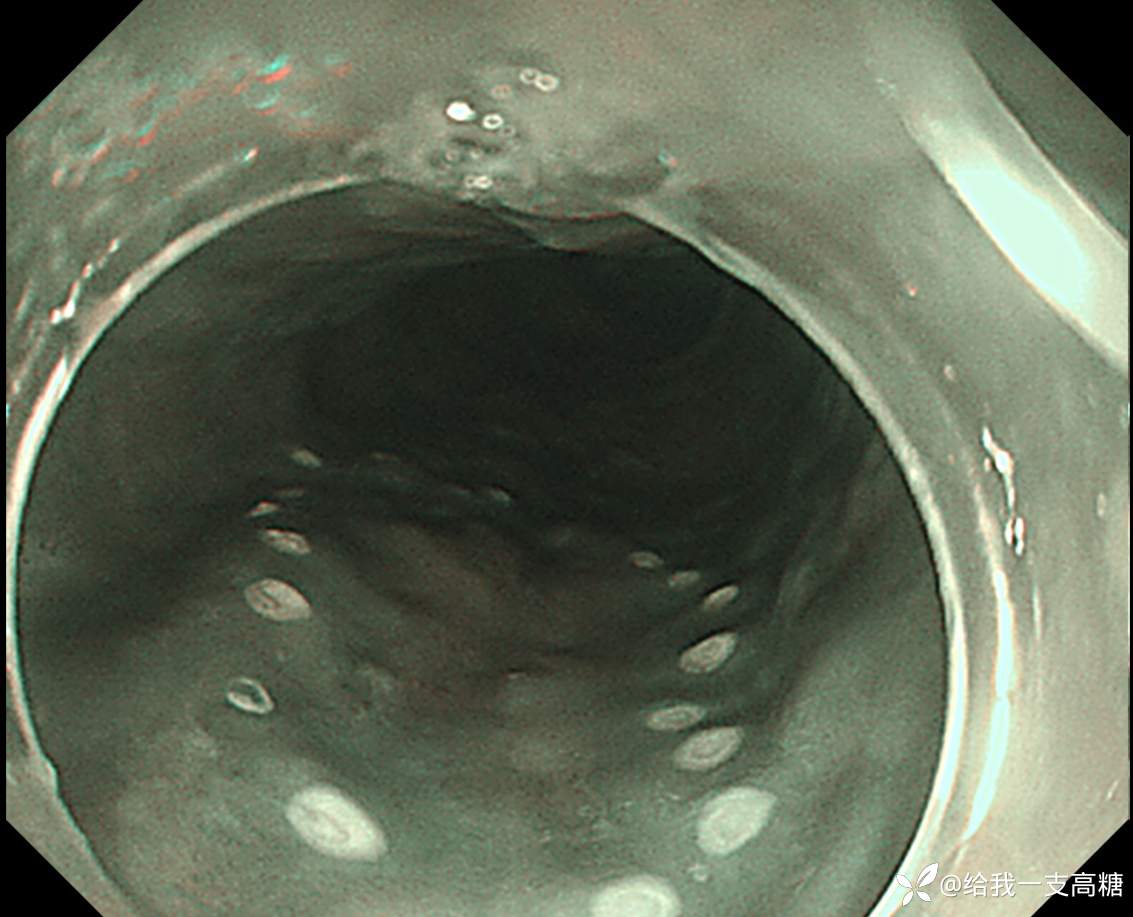

NBI下见局部IPCL B1

标记,口侧双标